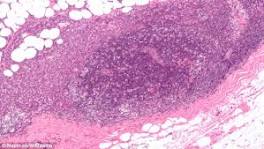

| Risk factors for gastric cancer of 'Risk factors for gastric cancer'. 2. PubMed. TI. A human model of gastric carcinogenesis. AU. Correa P. SO. Cancer Res. 1988;48(13):3554. AD.